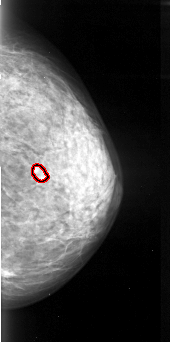

A_1057_1.LEFT_MLO

LEFT_MLO LINES 5401 PIXELS_PER_LINE 2641 BITS_PER_PIXEL 16 RESOLUTION 42 NON_OVERLAY

FILE: A_1057_1.RIGHT_MLO.OVERLAY

TOTAL_ABNORMALITIES 1

ABNORMALITY 1

LESION_TYPE MASS SHAPE OVAL MARGINS ILL_DEFINED

ASSESSMENT 4

SUBTLETY 4

PATHOLOGY MALIGNANT

TOTAL_OUTLINES 2

BOUNDARY

CORE